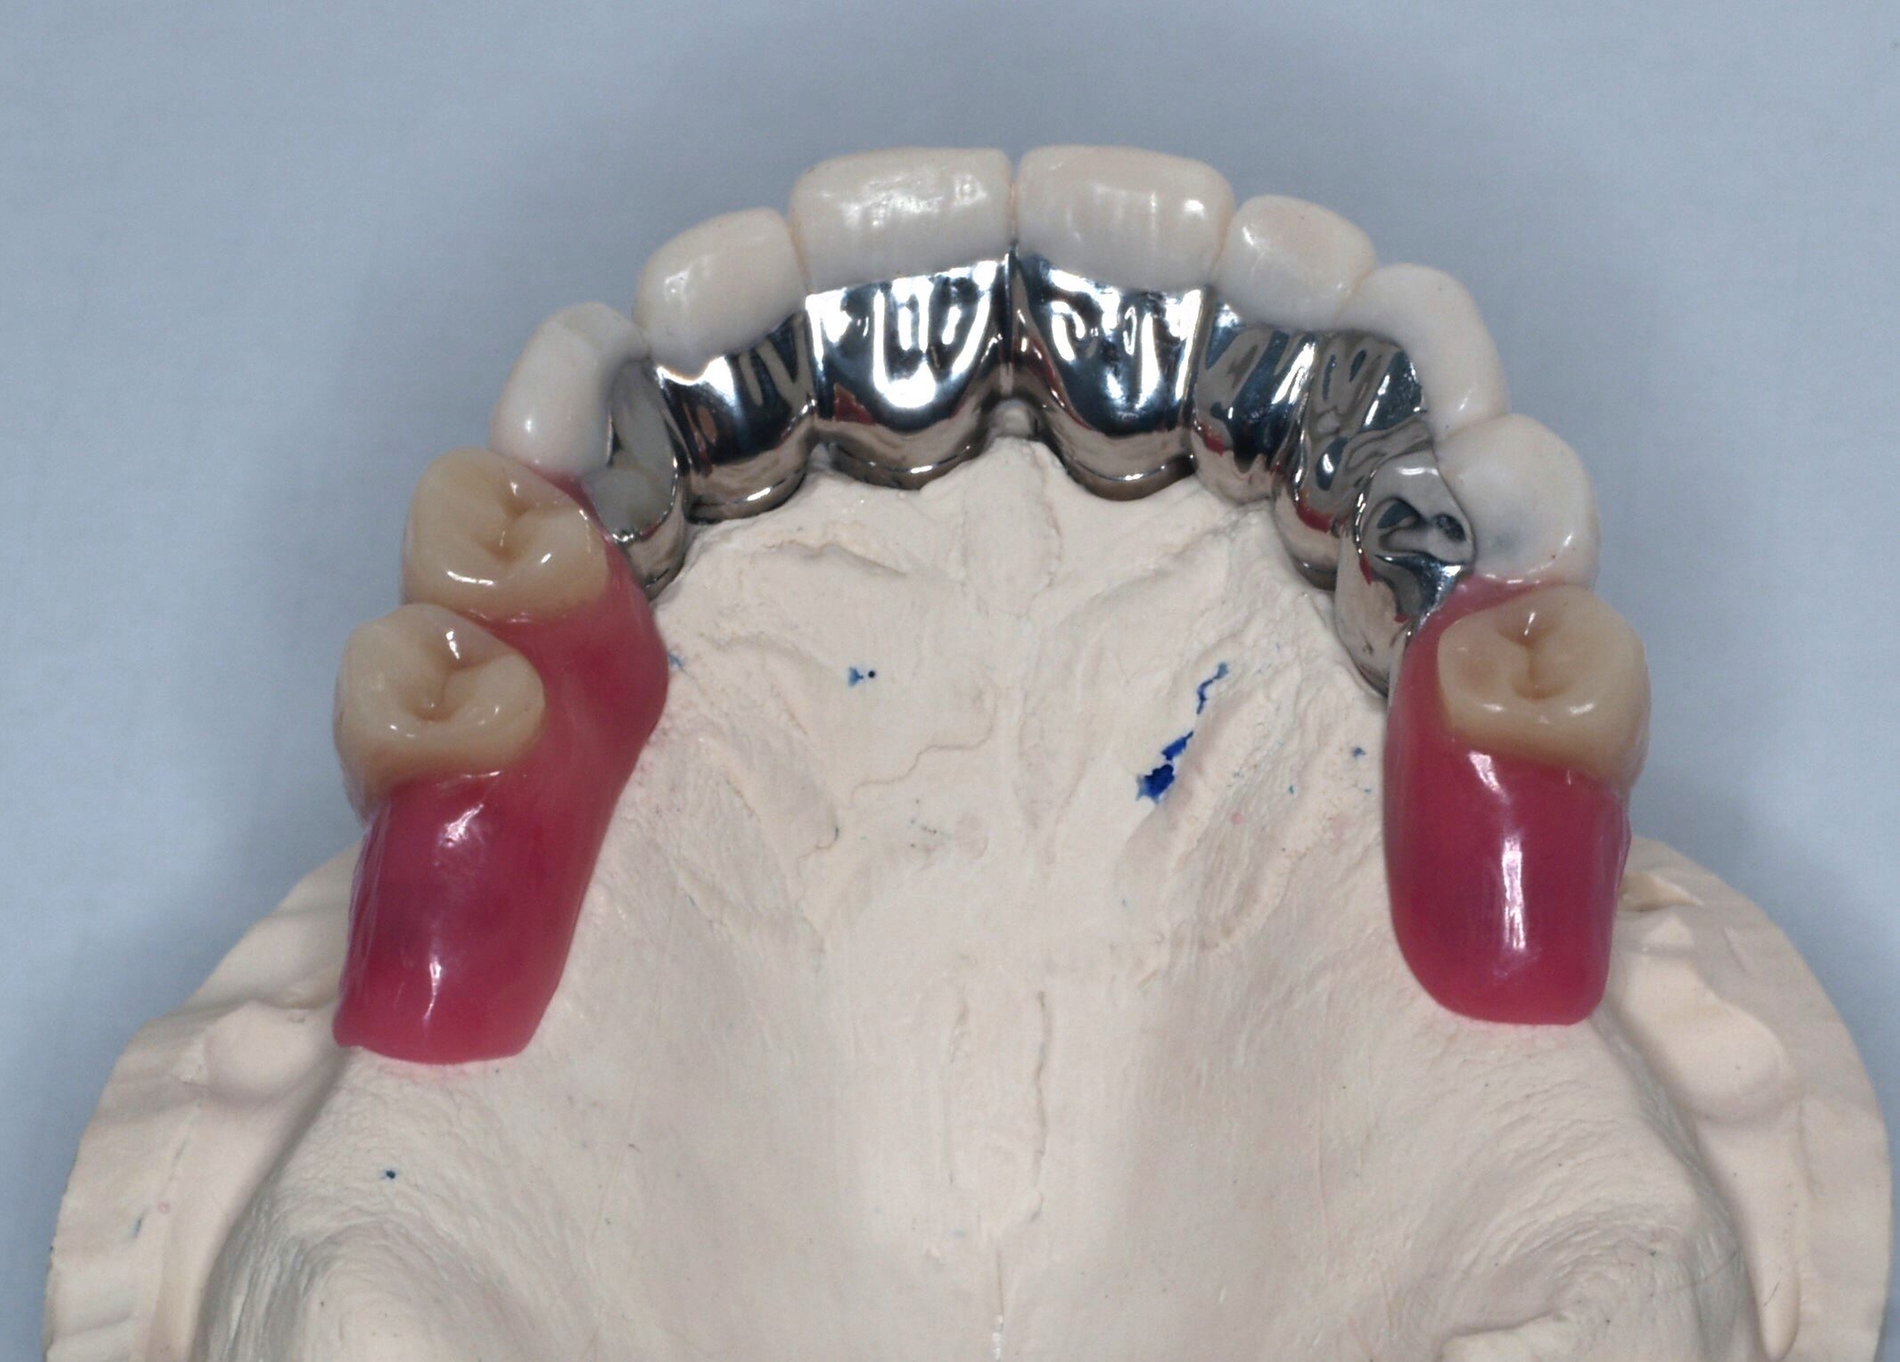

Auf dem Meistermodell wurde vom Labor nun der Wachswall zwecks Kieferrelationsbestimmung hergestellt. Nach Überprüfung der Ruheschwebelage von 2 mm wurde der Wachswall verschlüsselt. Bei der Gesamtanprobe konnte neben der Kontrolle der statischen/dynamischen Okklusion und der Ästhetik das spannungsfreie Gleiten des Prothesengerüsts in die Primärteleskope überprüft werden.

Schließlich erfolgte die Eingliederung der fertigen Teleskopprothese (Abbildung 6). Die Primärteile wurden mit Glasionomerzement auf den Stümpfen zementiert. Nach Entfernung der Zementreste und der erneuten Überprüfung der statischen und der dynamischen Okklusion, ist das gemeinsame Üben des Ein- und Ausgliederns der Prothese gerade bei dieser Art der Arbeit unabdingbar. Eine ausführliche Aufklärung über die Reinigung, Handhabung und das Recall folgte.